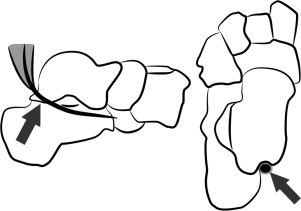

解剖